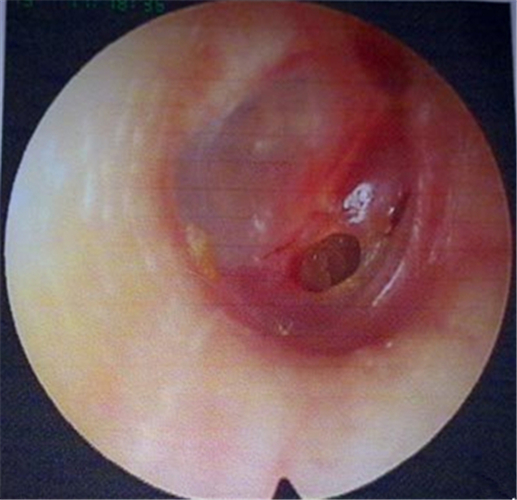

住院治療鼓膜穿孔